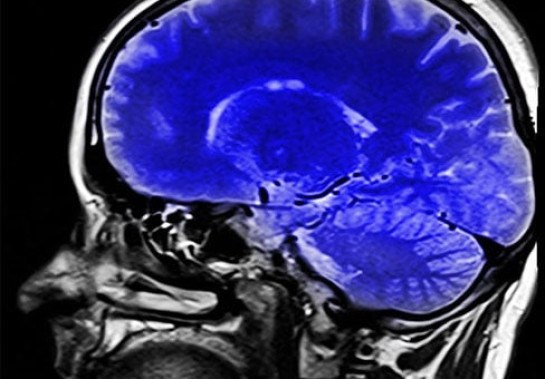

Pesquisadores de Harvard e Otago, na Nova Zelândia, desenvolveram uma ferramenta inovadora chamada DunedinPACNI, que pode medir a velocidade com que uma pessoa está envelhecendo usando apenas uma ressonância magnética do cérebro. A descoberta foi publicada na revista Nature Aging.

Para "ensinar" a ferramenta, os pesquisadores usaram as informações de uma única ressonância magnética cerebral, coletada de 860 participantes do Estudo Dunedin quando tinham 45 anos. Isso significa que um simples exame do cérebro pode agora revelar muito sobre como seu corpo está envelhecendo.